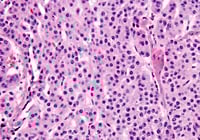

HE

Image

04_img03.jpg

シナプトフィジン